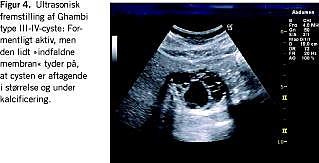

Polycystisk leversygdom er en sjælden benign, autosomal dominant sygdom med en prævalens på omkring 0,001%. Den findes oftest samtidigt med polycystisk nyresygdom. Tidligere anslog man, at ca. halvdelen af patienterne ville få leverkomponenten, men med forbedret overlevelse er andelen oppe på 70-90% [3]. Sygdommen forekommer hyppigere og er af større sværhedsgrad hos kvinder end hos mænd. Den fører stort set aldrig til leversvigt, og symptomerne er overvejende relateret til de polycystiske organers størrelse og fylde med tyngdefornemmelse, mavesmerter, kvalme, opkastninger, tidlig mæthedsfornemmelse, åndenød og evt. obstruktionsicterus. Leverens vægt udgjorde mediant 9% af legemsvægten i en dansk opgørelse af levertransplanterede [4] mod normalt 2%. Sygdommen kan inddeles efter udbredelsen og størrelsen af cysterne (fra grad I; få store cyster (< 10) til grad IV; multiple små til mellemstore cyster diffust i leveren) (Figur 2 ).